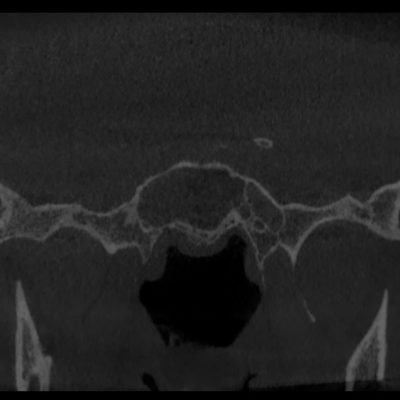

Перші шість знімків відносяться до першої операції, решта – до другої